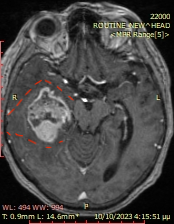

Το δόγμα της σύγχρονης χειρουργικής όγκων απεικονίζεται στις μαγνητικές αυτές. Στόχος μας είναι η μέγιστη δυνατή ασφαλής αφαίρεση του όγκου. Δεν πρέπει να στοχεύουμε στην εξαίρεση όχι μόνο του όγκου, όπως φαίνεται στην μαγνητική αλλά και στην αφαίρεση και της διηθητικής ζώνης και της υγιούς περιβάλλουσας περιοχής αν αυτή δεν έχει λειτουργίες. Η εικόνα 1α είναι προεγχειρητική, εδώ έχει σχεδιασθεί το εύρος της στοχευμένης εξαίρεσης. Η εικόνα 1β δείχνει το μετεγχειρητικό αποτέλεσμα μιας υπερολικής εξαίρεσης. Πρόκειται για την πρώτη ασθενή που χειρουργήθηκε στην Ελλάδα από τον Καθ. Γούσια τον Οκτώβριο του 2023, η οποία διαγνώσθηκε με την πιο επιθετική μορφή του γλοιοβλαστώματος, το λεγόμενο γλοιοσάρκωμα, η οποία 20 μήνες μετά την χειρουργική επέμβαση παραμένει χωρίς ένδειξη όγκου στην μαγνητική και το πιο σημαντικό χωρίς νευρολογικά ελλείμματα.